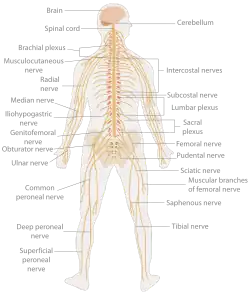

Neurologie (z řeckého νεῦρον, neuron, „nervy“ a -λογία, -logie, „-věda) je lékařský obor zabývající se studiem onemocnění a poruch nervové soustavy především na organickém podkladě. Zabývá se diagnostikou a léčbou všech problému centrální, periferní a autonomní nervové soustavy. Lékař tohoto oboru se nazývá neurolog/neuroložka. Neurologie velmi úzce souvisí s psychiatrií, interním lékařstvím, ale i s pediatrií. Dětská neurologie je, kvůli řešení specifických problémů, samostatným lékařským oborem. S neurologií úzce souvisí specializovaný obor neurochirurgie, ten se však zabývá řešením onemocnění a úrazů nervového systému chirurgickou cestou.

Neurologické vyšetřovací metody spočívají především ve vyšetření:

- držení těla, chůze, napětí svalů a schopnosti regulovat svalové napětí

- vyšetření senzitivních nervů zkouškami kožní citlivosti

- vyšetření senzorických nervů zkouškami smyslů